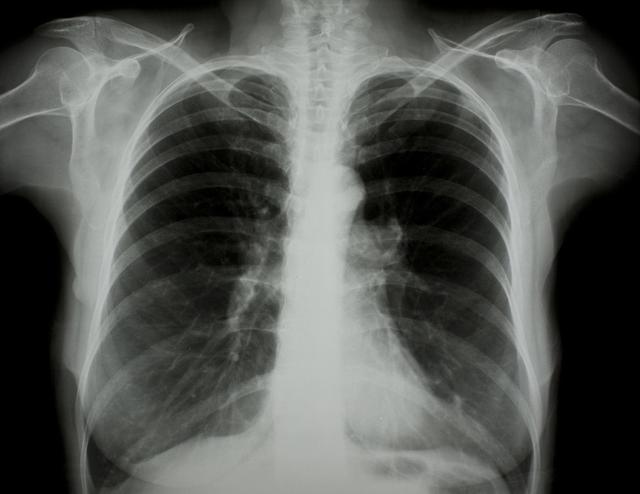

涪陵地區(qū)最新肺炎情況顯示,疫情形勢嚴峻。目前,當?shù)卣歪t(yī)療部門正在積極應對,采取一系列措施控制疫情傳播。具體感染人數(shù)、癥狀表現(xiàn)、疫苗接種情況等仍在持續(xù)更新中。請廣大市民密切關注官方發(fā)布的信息,做好個人防護,共同抗擊疫情。涪陵地區(qū)肺炎疫情嚴峻,政府積極應對,請市民關注官方信息,加強個人防護。

據(jù)最新官方數(shù)據(jù)顯示,涪陵地區(qū)肺炎病例數(shù)量令人擔憂,截至目前,涪陵地區(qū)累計確診肺炎病例XX例,疑似病例XX例,請大家務必提高警惕,不可掉以輕心。